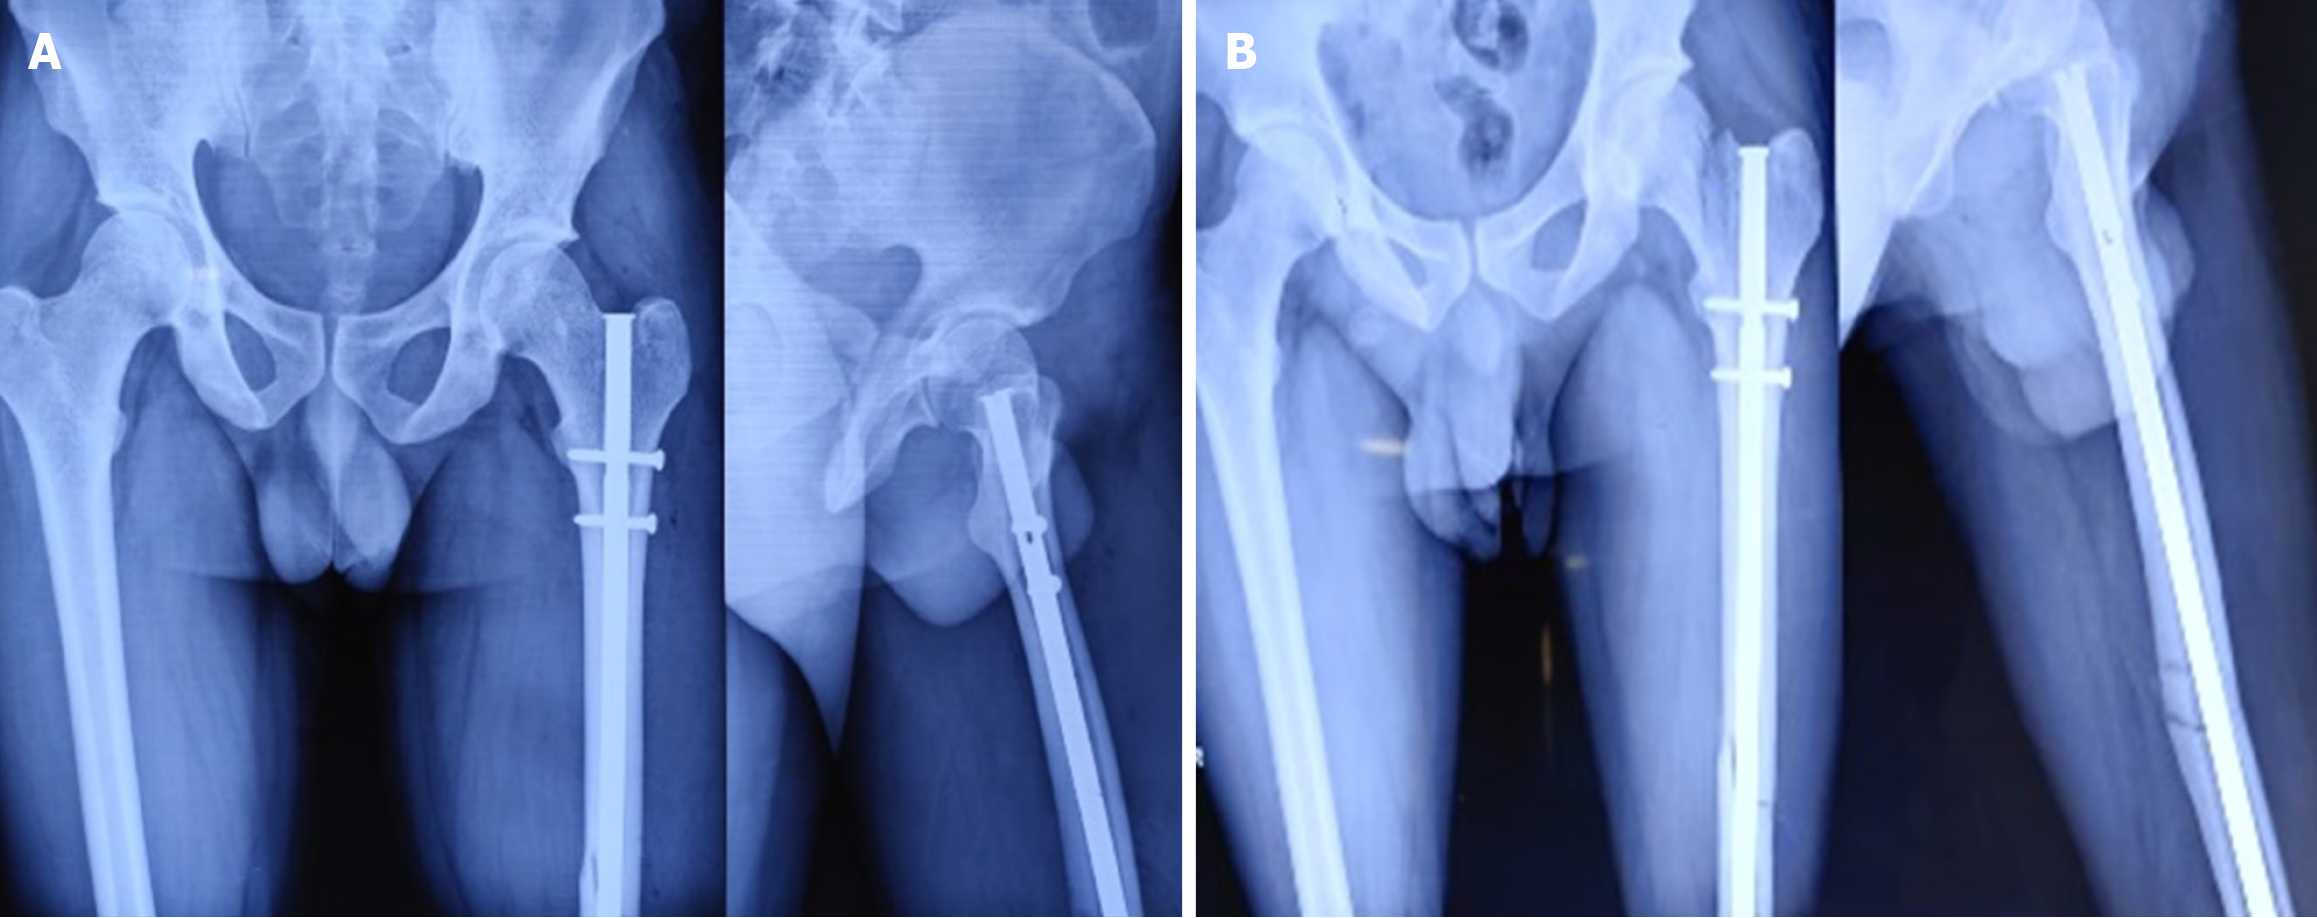

Among the 18 cases, 11 were undisplaced and 7 were displaced. Fixation methods included long proximal femoral nails (10 cases), cannulated cancellous screws (6 cases) as shown in Figure 6, bipolar hemiarthroplasty (1 case) as shown in Figure 7, and dual implant technique with limited contact dynamic compression plate (1 case) as shown in Figure 7. The “miss-the-nail” technique was employed in cases where the interlock nail remained in situ and removal was deemed risky due to potential displacement as shown in Figure 5 and Table 2.

Fractures were diagnosed intraoperatively in 14 cases, immediately postoperatively in 1 case, and during follow-up (within 4 weeks) in 3 cases. The etiological breakdown included erroneous entry point (6 cases) as shown in Figure 3, inadvertent jig hammering (5 cases) as shown in Figure 4, misdirected nail manipulation (3 cases), hoop stress-related fractures (3 cases) as shown in Figure 5, and one case of unexplained origin. Intraoperative fractures were typically identified during final fluoroscopic checks, while postoperative fractures were detected on follow-up radiographs without intervening trauma Figure 6. The list of eitiologies contributing to iatrogenic fractures during femoral nailing is listed in Table 1.